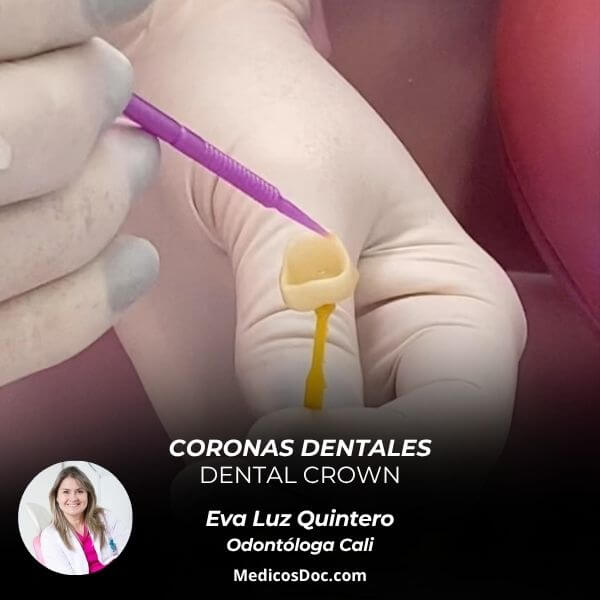

The specialties of Eva Luz Quintero are: Dentist, Cosmetic dentistry, Orthodontics, Oral rehabilitation, Periodontics, Endodontics, Oral and maxillofacial surgery, Dental implant, Geriatric dentistry, Prosthodontics.